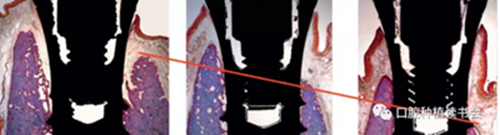

圖2 動(dòng)物實(shí)驗(yàn)的病理切片顯示

即刻種植后骨板發(fā)生了顯著吸收

最初做即刻種植是為了預(yù)防牙齒拔除后牙槽窩的改建,但后來(lái)事實(shí)證明并非如此。Araújo 和 Lindhe的動(dòng)物實(shí)驗(yàn)表明,拔牙后3周牙槽骨板平均發(fā)生垂直吸收2.6mm。Botticelli 等獲得了類(lèi)似的動(dòng)物實(shí)驗(yàn)研究結(jié)果,拔牙4個(gè)月后,垂直骨吸收達(dá)2.8mm(圖2),這些研究均表明牙齒拔除之后無(wú)論是否即刻種植,拔牙窩頰側(cè)、舌側(cè)骨板都會(huì)發(fā)生大量的骨改建。